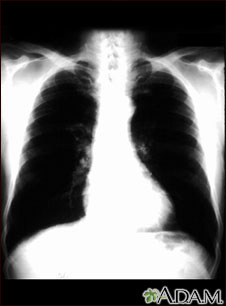

Ésta es una radiografía de tórax de una persona con cáncer bronquial. En esta vista frontal, los pulmones aparecen como dos áreas oscuras y el corazón y otras estructuras como las áreas claras visibles en la mitad del tórax. Las áreas claras que aparecen como ramificaciones sutiles extendiéndose desde el centro hacia los pulmones son cancerosas.